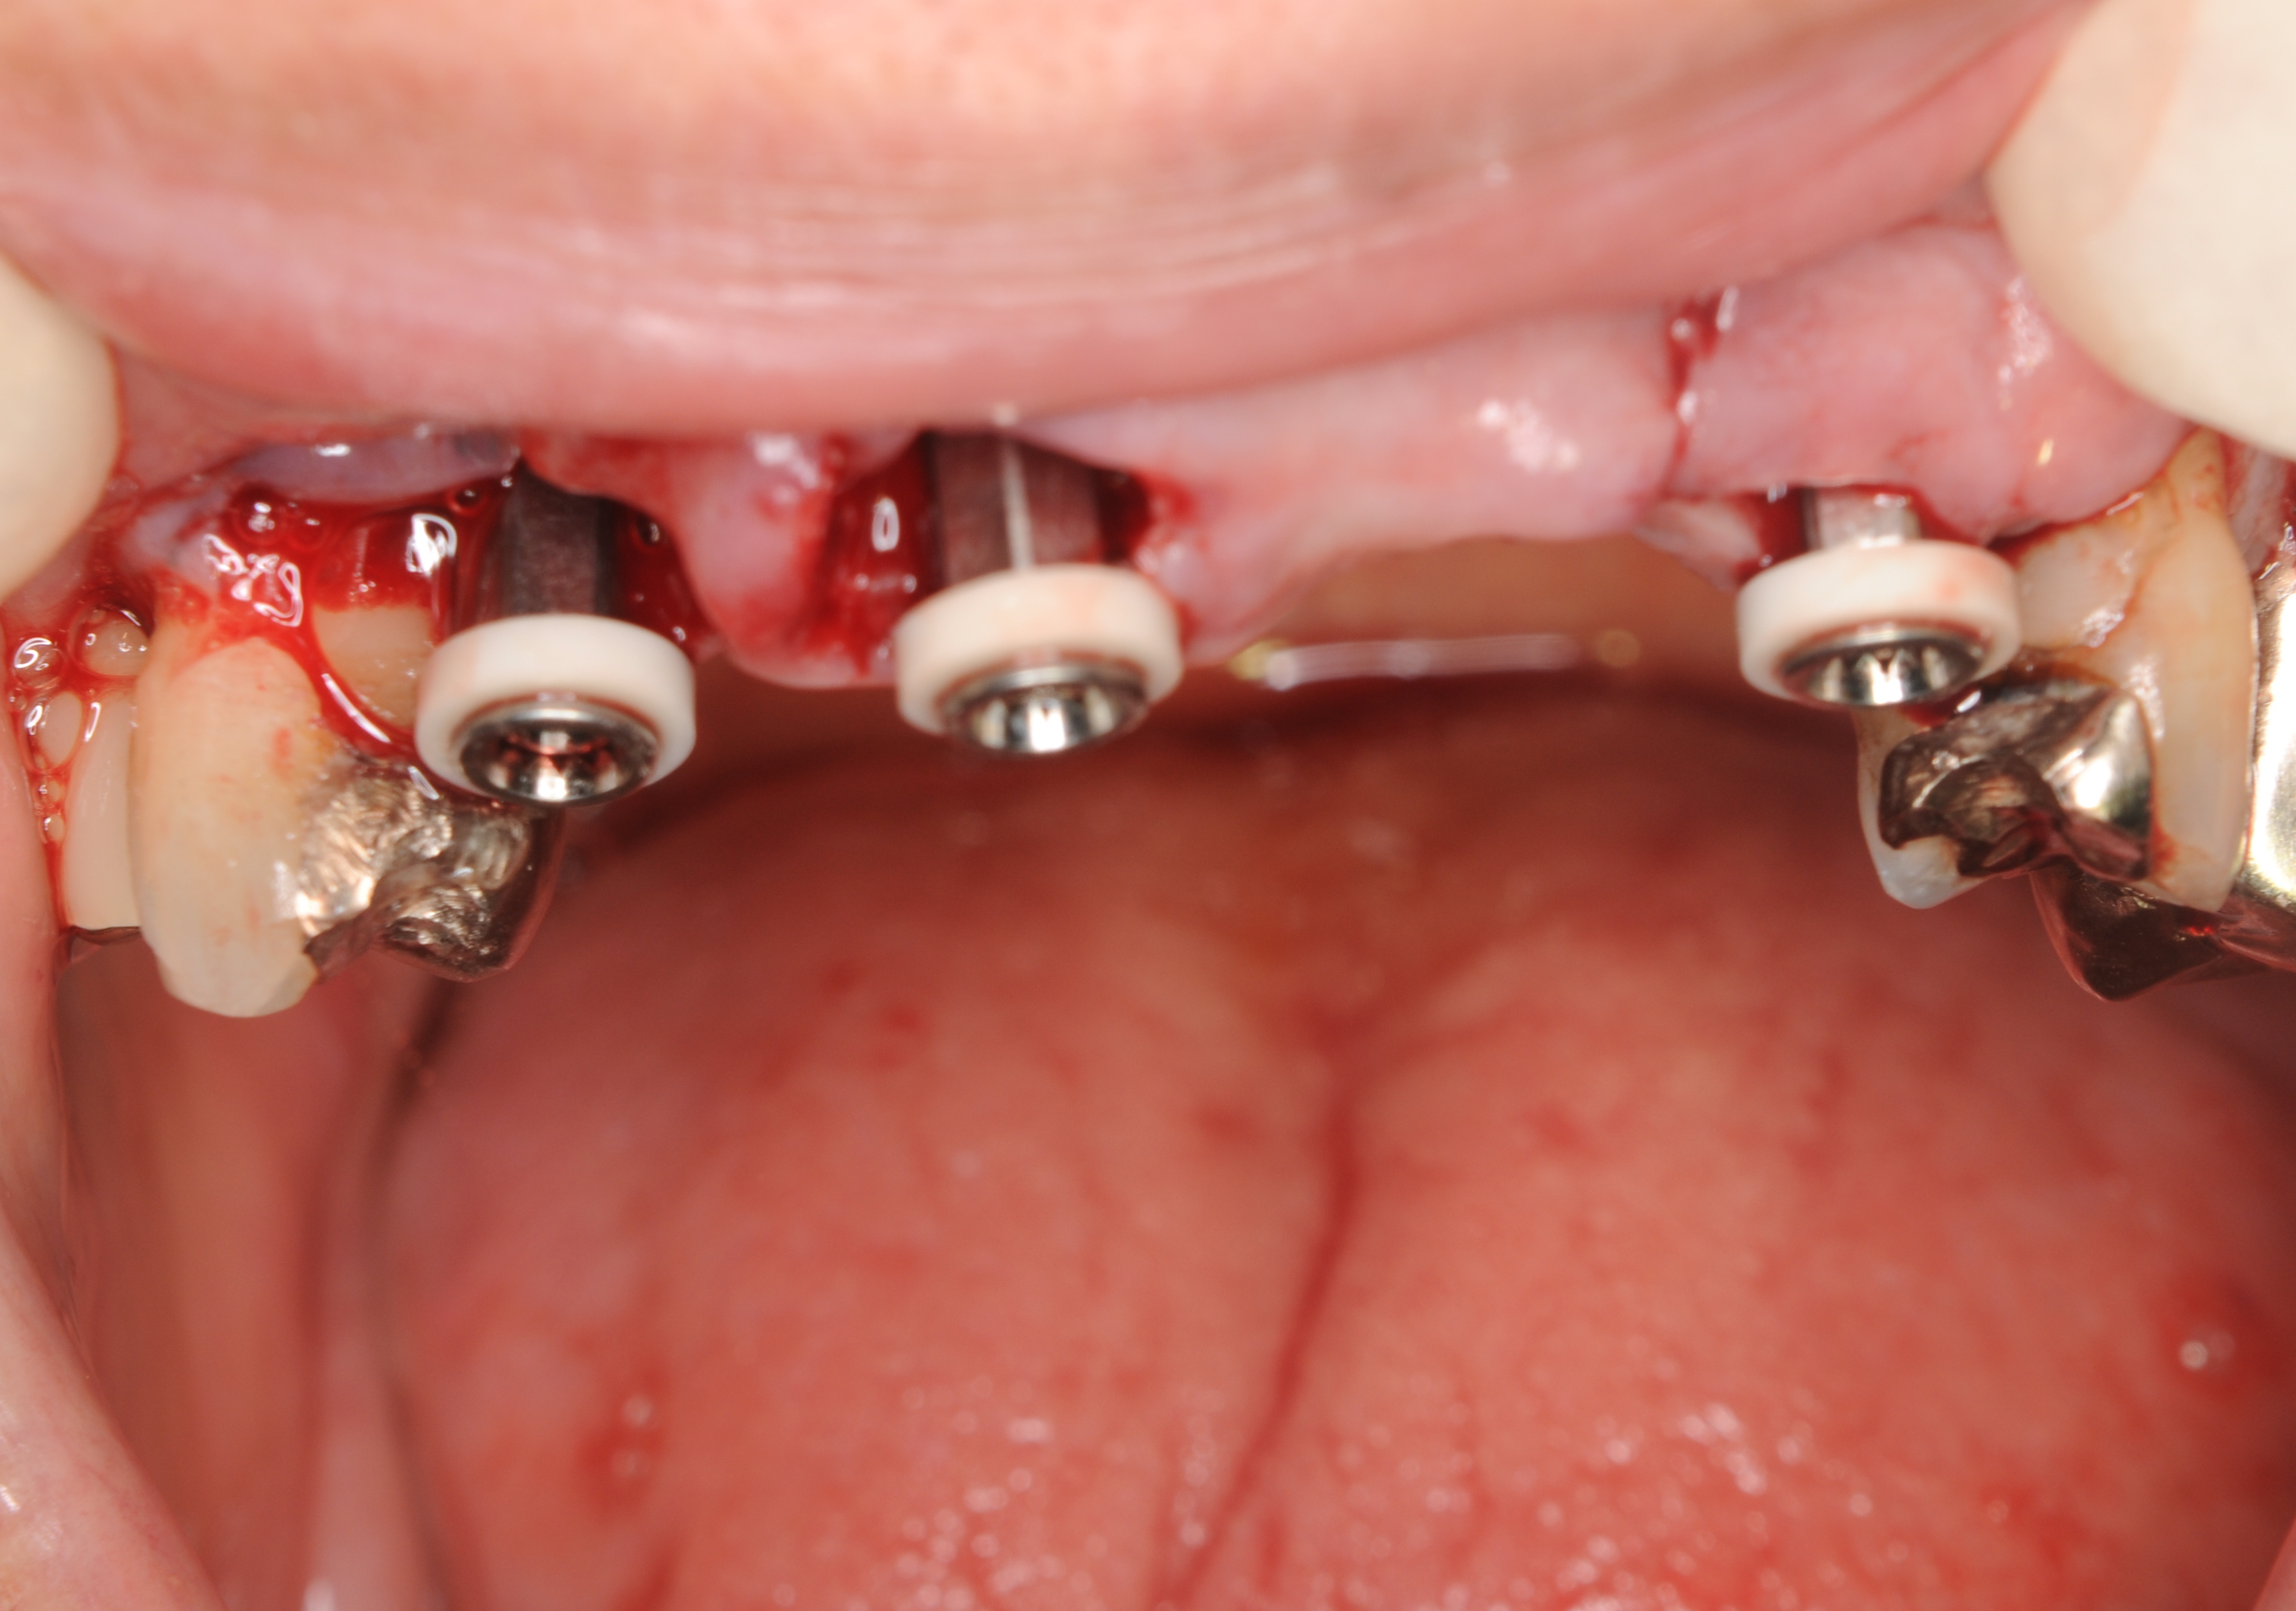

次の2症例は抜歯即時埋入インプラントです。

歯ぐきは切開していないことがご理解していただけると思います。

抜歯窩にインプラントを埋入しますので、

まわりの歯ぐきを通常のインプラントのように切開する必要が

ありませんで、インプラント手術後の痛みや腫れも少ないという

利点があります。